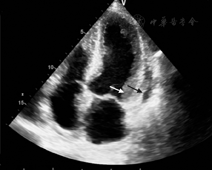

进一步完善检查,血沉81 mm/h,C反应蛋白92.3 mg/L (正常值<8.0 mg/L)。免疫球蛋白七项:IGA 5.5 g/L(正常值0.7~3.8 g/L),IGE 770.6 g/L (正常值<100 g/L),IGG、IGM、总补体、补体C3和补体C4正常。髓过氧化物酶抗中性粒细胞胞质抗体(MPO-ANCA)、丝氨酸蛋白酶3抗中性粒细胞胞质抗体(PR3-ANCA)、抗核抗体、抗ENA抗体谱、抗dsDNA抗体和抗脑组织抗体均为阴性。便常规、肝功能、肾功能、甲状腺功能、凝血功能均未见异常。超声心动图示心内膜略增厚,左心室内血栓前状态[1],左心房增大,室间隔增厚(12.2 mm),左心室舒张功能减退,左心室射血分数(LVEF) 55%,心包积液(少量)伴纤维素渗出(图3)。支气管肺泡灌洗液的细胞中嗜酸粒细胞占97%,提示存在肺部嗜酸性粒细胞浸润。复查胸部CT较1个月前无明显变化。颅脑磁共振成像示双侧半卵圆中心、右侧侧脑室后角见斑点状高信号影。肌电图示右腓总神经复合肌肉动作电位(compound muscle action point,CMAP)未测出,左腓总神经、双胫神经远段CMAP波幅下降,左三角肌、双股四头肌示肌源性损害,提示患者存在神经及肌肉损害。肌肉、神经、皮肤活检病理示左腓肠肌中度肌源性损害,左腓总神经损害以髓鞘改变为主,筋膜及皮肤可见间质小血管壁炎症细胞浸润,以淋巴细胞为主,偶见嗜酸性粒细胞。骨髓穿刺示嗜酸粒细胞增多,较成熟。基因分型未见FIP1L1-PDGFRα融合基因。荧光染色体原位杂交未发现FIP1L1/PDGFRα融合基因、未发现PDGFRB基因重排。

根据1990年美国风湿病协会Churg-Strauss综合征的诊断标准[2],该例患者最终诊断为嗜酸性肉芽肿性多血管炎。受累系统包括心脏(嗜酸性粒细胞浸润导致的心肌炎、心内膜受累导致左心室血栓前状态、心包炎)、呼吸系统、中枢和外周神经系统、肾脏。予静脉应用甲泼尼松龙200 mg 3 d、80 mg 3 d,后改口服56 mg/d (0.8 kg·mg-1·d-1);环磷酰胺0.1 g口服,隔日1次。由于患者左心室存在血栓前状态,给予低分子肝素过渡到华法林抗凝。治疗6 d后复查血常规,嗜酸粒细胞百分数降至0.01%。随访6个月患者临床症状缓解,复查心电图示V4~V6导联ST压低程度减轻,Ⅰ、Ⅱ、V4~V6导联T波低平。超声心动图示心内膜增厚及左心室血栓前状态消失,三尖瓣反流(轻度),左心室舒张功能减退,左心房压升高,LVEF为71%。

有心脏受累临床表现的患者约占到嗜酸性肉芽肿性多血管炎的27%~47%,而存在心电图和超声心动图异常的患者达到62%[6]。心脏受累是EGPA患者死亡及预后较差的主要原因[7]。EGPA心脏受累可表现为心内膜炎、心包积液、心律失常、收缩性心力衰竭[5],也可引起冠状动脉血管炎导致心肌梗死等[8]。本例患者心电图多导联ST段压低、T波倒置,心脏标记物轻度升高,类似NSTEMI,但入院后多次行心电图未见明显动态演变,心脏标记物轻度升高,但下降缓慢,符合急性心肌炎的心脏标记物的变化特点,与急性心肌梗死的表现不同,并经冠状动脉造影除外了冠状动脉严重狭窄所致。虽然没有心肌活检的证据,但推测患者存在嗜酸粒细胞性心肌炎,而并非EGPA引起的冠状动脉血管炎。除心肌受累外,入院后该患者超声心动图发现心内膜增厚,左心室内血栓前状态,心包积液(少量)伴纤维素渗出,提示还存在心内膜和心包受累。